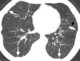

Calcified pleural plaque